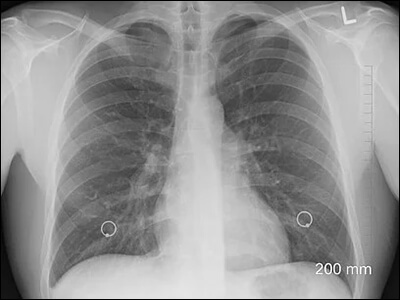

많은 분들이 가슴 통증 원인으로 심장 질환을 의심합니다. 하지만 가슴에는 폐와 내부 기관을 보호하는 근골격이 있으며 그 부위에 문제가 생겨 통증이 발생하는 경우가 많이 있습니다. 갈비뼈 골절 등은 사고로 인해 발생한다고 생각하지만 염증으로 인한 통증도 염두에 두시기 바랍니다.

1) 폐색전증

호흡기계 중 가슴통증 원인이 되는 증상으로는 폐색전증을 이야기할 수 있습니다. 폐색전증은 폐에 혈액을 공급해주는 혈관이 막혀 혈액 공급이 줄어들거나 막히는 경우에 생길 수 있습니다. 이 경우 호흡곤란 및 가슴 통증을 유발합니다. 또한 숨을 들이마시거나 기침을 하게 되면 찌르는듯한 통증이 심해지며, 고열을 동반하는 경우도 있습니다.